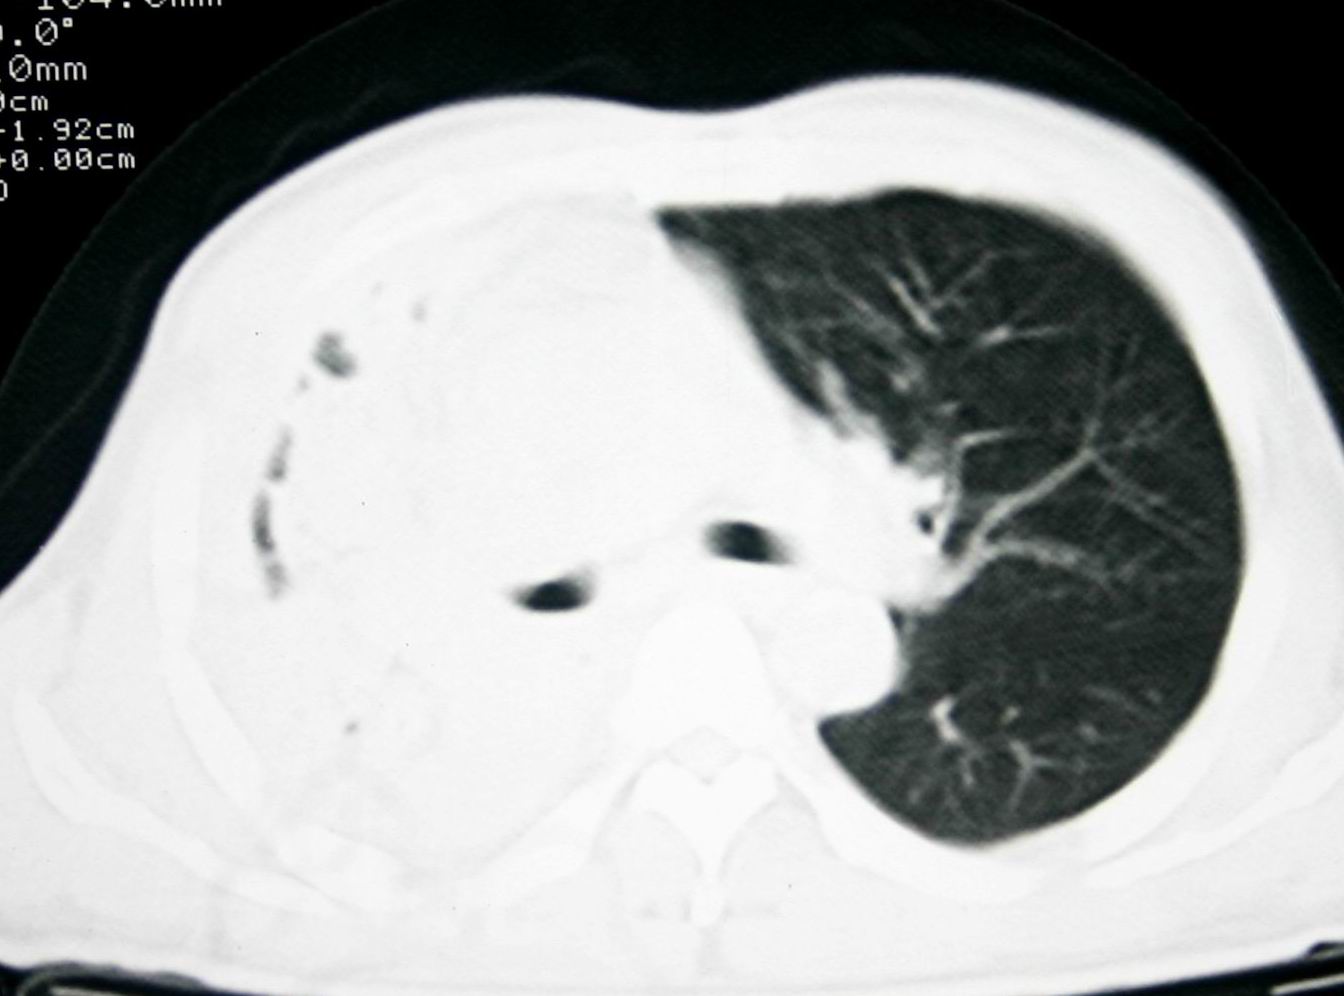

患者,男 ,48岁,反复咯血三个月,每三到五天咯一次,每次约200ml,鲜红色,无明显咳痰,咳嗽明显,无明显胸痛,无发烧,初期以抗感染、止血治疗,第一次ct报占位,支气管镜未见明显ca细,肺ca标志物、tb抗体均阴性,经过垂体后叶素、酚妥拉明、头胞他定、洛美沙星、立止血等治疗后,现病人一般情况好,停止咯血10天,咳嗽减少,咳黄脓痰,每日一次,每次30ml。现复查ct

右肺膨胀不全,纵隔右侧移位。肺内有感染,胸腔有积液。建议老片对比。

1)考虑右肺继发性肺结核合并感染。2)右侧胸腔积液+胸膜增厚。

支持:右肺膨胀不全,纵隔右侧移位。肺内有感染,胸腔有积液。建议老片对比。